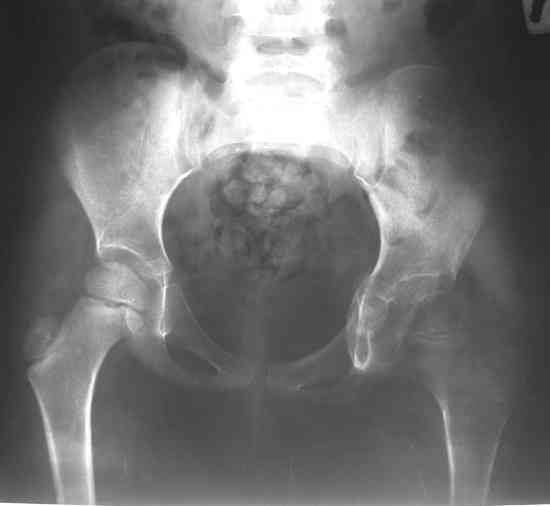

После операции ребенок находился в гонитной повязке три недели. Затем повязка снята. На контрольной рентгенограмме выявлен вывих левого бедра. Наложена система скелетного вытяжения за левое бедро. Через две недели система снята, наложена шина Веленского. Вопросы: 1. Тактика дальнейшего лечения? 2. Какое оперативное лечение оптимально предпринять? Заранее благодарю! С уважением, А.В.Владзимирский ДНИИТОDear colleagues! Female, 5 y.o. During 1 year she has pain and limitation of movements in left hip. DS: Osteochondroma of left hip. 26.07.07. surgery: arthrotomia, removing of osteochondroma, plastic of defects with “Tutoplast”, cast fixation. Cytology: parts of hyalin cartilage with sponge bone and marrow. Most possible – osteochondroma, osteochondro exostosis. Cartilage tissue not looks like typical chondroma. After 3 weeks cast fixation was removed. At x-ray – dislocation. Dislocation was treated by sceletal traction (2 weeks). Now – dislocation again. Question: Treatment? Which surgical treatment most useful in this situation? Thank you very much for your comments, opinions, ideas!!! Best wishes, Anton Vladzymyrskyy

2. Судя по представленному снимку, образование находилось внутрисуставно, а кости таза не поражены (что тогда заполнялось тутопластом? и не он ли, судя по п\о рентгенограмме явился причиной вывиха?).

Уважаемый коллега. Что же заставило Вас со столь скудными рентгенограммами решиться на обширное вмешательство? Состояние головки бедра перед операцией не совсем понятно. Отчего не сделать было хотя бы артропневмографию тазобедренного сустава? Описание операции какое-то поверхностное. Где в вертлужной впадине было обнаружено новообразование? Откуда исходило и какой объём занимало? Куда девался наружный край впадины (или это и есть тутоген)? Почему и из каких соображений была выбрана "гонитная" повязка? Что было на послеоперационных снимках?

А бедро надо возвращать ко впадине дистракцией, иначе в дополнение к впадине и головку угробить недолго. Видимо в дальнейшем не обойтись без пластики наружного края вертлуги.